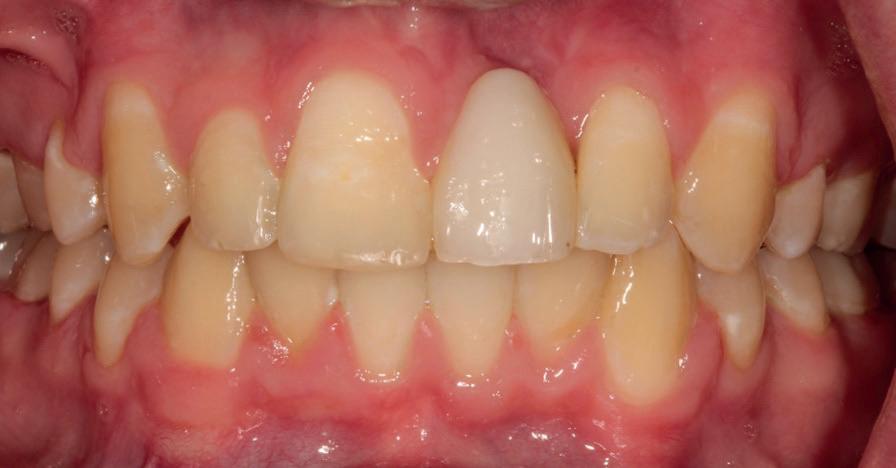

RECONFIGURAREA suportului osos implantar. În cazul prezentat, după ani de terapie ortodontică incorect executată, dezvoltarea dentară a pacientului a complicat obținerea unui zâmbet estetic. S-a reanalizat și s-a optat pentru abordare interdisciplinară care cuprinde chirurgia parodontală, un al doilea tratament

ortodontic și protetica pentru a oferi îngrijirea comprehensivă.